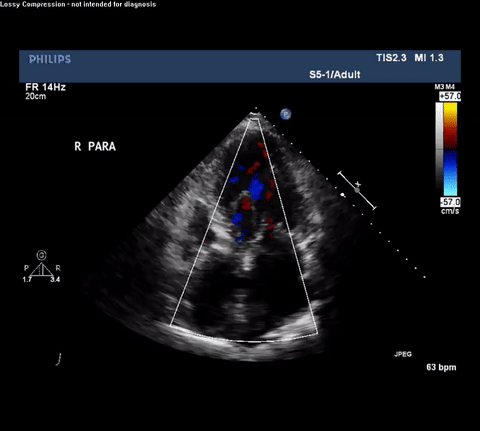

Cardiac point-of-care ultrasound (POCUS) was performed and a representative video was obtained.

TTE Parasternal Long Axis View

Type A acute aortic dissection (TA-AAD). Cardiac POCUS imaging in the

parasternal long axis revealed the intima of the ascending aorta undulating in

and out of the left ventricular outflow tract throughout the cardiac cycle,

consistent with a TA-AAD.

TTE Apical Four Chamber View With Doppler

Despite these shortcomings, cardiac POCUS can be performed quickly and does

not require either transport or IV contrast. This case illustrates how

intensivists performing routine cardiac POCUS exams need to be able to

identify both direct and indirect signs consistent with TA-AAD or else an

opportunity to provide expedited care may be missed. For example, it is

important to recognize the presence of an intimal flap which must be

differentiated from reverberation or mirror artifact originating from nearby

structures. Color Doppler can aid in identifying both true and false lumens

along with aortic regurgitation. Finally, depending on the clinical setting

other findings may be associated with TA-AAD and should raise concern for this

diagnosis including: bicuspid aortic valve, dilated aortic root, aortic

regurgitation and pericardial effusion.